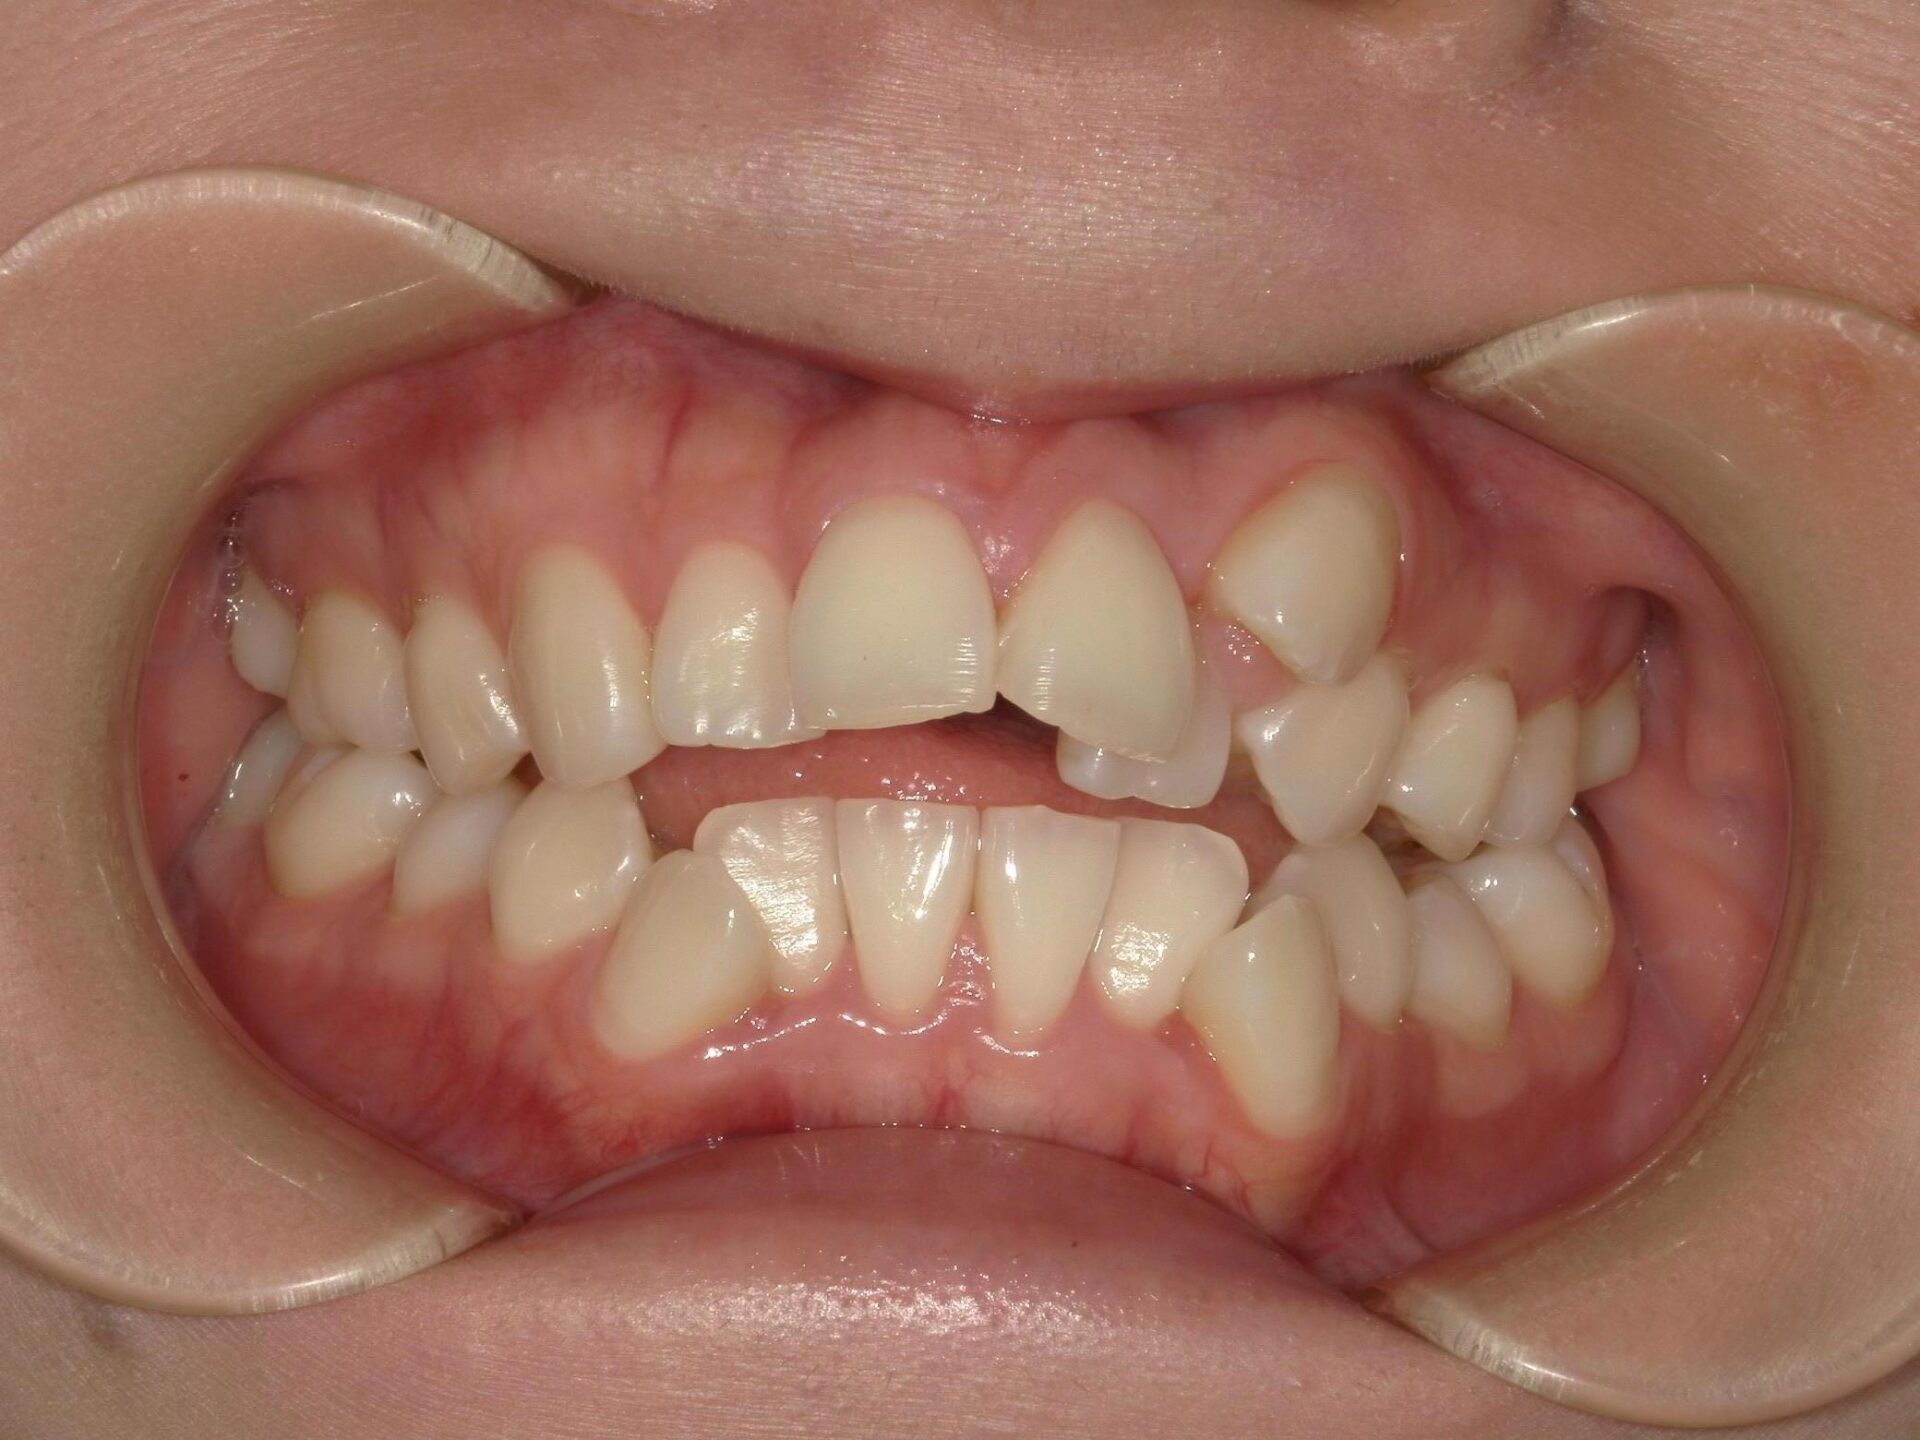

20代、女性、ワイヤー

| 施術内容 | 主訴:全体的に凸凹が気になる 詳細:ワイヤー矯正での歯並び改善 ずっと磨きにくく、臭いが気になっていましたが、 矯正後は磨きやすくなり、臭いも無くなって満足された症例です。 |

| 治療期間 | 16ヶ月(3/13現在 治療終了) |

| リスク・副作用 | ■リスク・副作用 ・治療の初期段階では、痛みや不快感が生じやすくなりますが、一週間前後で慣れます。 ・歯の動き方には個人差があるため、予想された治療期間より延長する場合があります。 |

| 費用 | ワイヤー矯正 60万円(税込660,000円) |